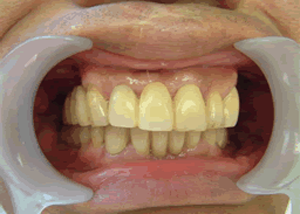

19.下は作った最終本物の歯が入りました。

これで治療終了。

開口器を入れた口元

治療完了

平成21年1月29日

(治療期間:1年7ヶ月)